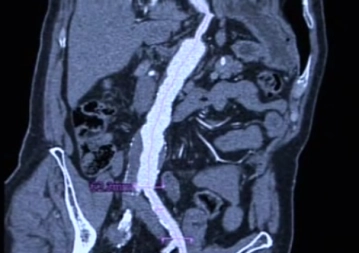

• TC abdominal con contraste (Angio-TC) para la representación del tamaño y la morfología del aneurisma

observación en medicina intensiva dependiendo de las enfermedades concomitantes; control de laboratorio (Hb, coagulación, creatinina); control por TC antes del alta; control por TC renovado después de 6 y 12 meses, en caso de hallazgos normales luego anualmente; aclaración angiográfica en caso de endoleaks, migración y dislocación de la endoprótesis, aumento de tamaño del aneurisma.